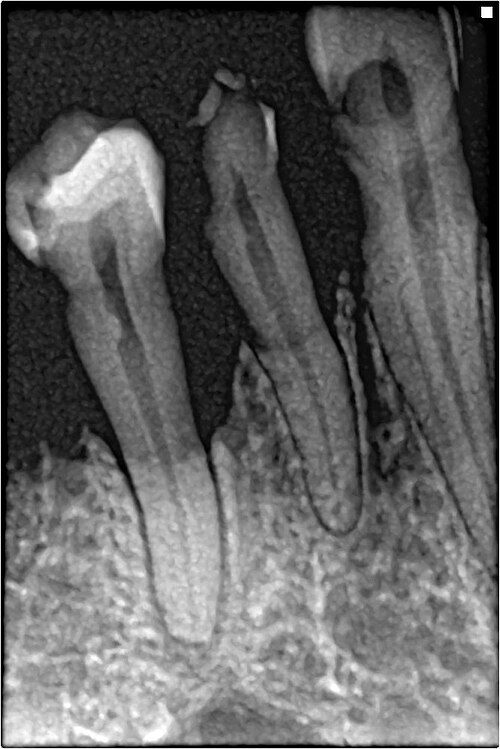

Dental phantom showing common pathology: carious lesions, periapical abscess, root resorption, and a metallic restoration